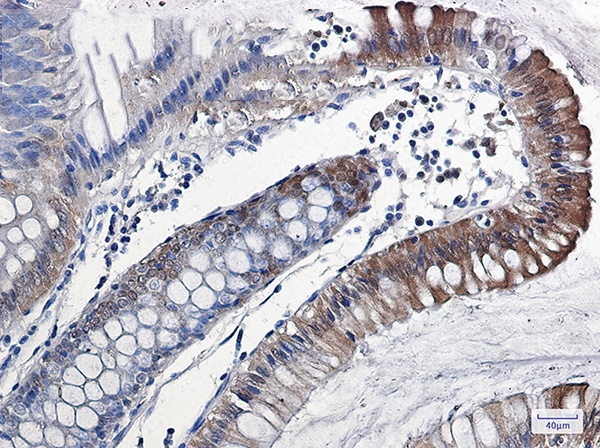

Immunohistochemistry of IL-18 in paraffin-embedded Human colon cancer tissue using IL-18 Rabbit mAb at dilution 1/50